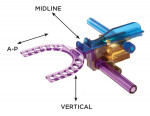

All patients were titrated using the AMPG (Figure 1) by a dentist trained and experienced in sleep dentistry. The device is designed to engage the upper and lower incisors in polycarbonate cradles. Edge-to-edge occlusion for A-P movement is defined as the zero position. Because of the incisor cradle thicknesses, the closed vertical position of the AMPG represents a 2 mm vertical opening as the minimum vertical position.

The AMPG is designed to allow for 7 mm anterior to 5 mm posterior adjustments and from 2 mm to 9 mm vertical adjustments. It can be adjusted via the patient’s mandibular movement or driven by the dentist via a rack and pinion gear set for each A-P and vertical axis. Each axis can be locked once a preferred position has been achieved. The AMPG device used in this study also has a +/- 3 mm sagittal movement option that was not implemented as part of the study. The gauge is polycarbonate allowing it to be used in conjunction with radiological instruments.